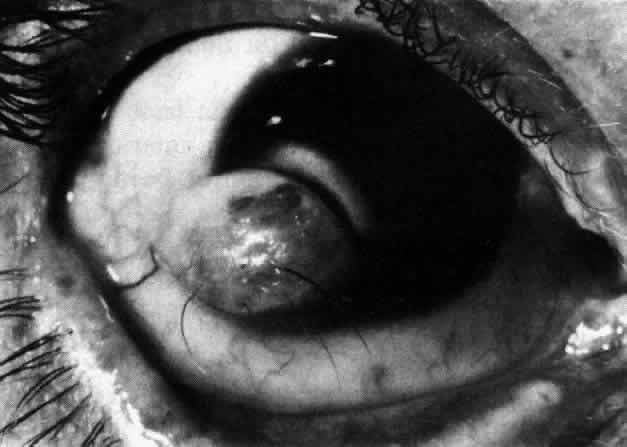

Myopia, ptosis, megalocornea, and blue scleras have all been reported frequently in these patients. Strabismus is likewise extremely common, but its presence alone does not suggest the diagnosis. The anterior segment structures exhibit both subtle and gross changes, some of which (especially in combination) are extremely suggestive of Marfan's syndrome. The anterior chamber angle exhibits an immature ciliary body with hypoplasia of the muscular elements, a very broad trabecular meshwork, and an inconspicuous Schwalbe's line. Transillumination demonstrates that the iris has a very posterior insertion on the ciliary body, the processes of which extend radially behind the iris much more than usual. The iris tends to show no circumferential ridges, few crypts, and, occasionally, iris root cysts, while iridodonesis occurs when the lens is subluxated. One peculiar abnormality is a hypoplasia of the iris dilator muscle; this causes the pupil to remain small even in response to mydriatic drops. The principal lenticular anomaly is ectopia lentis. This is found in the vast majority of patients with Marfan's syndrome; it is usually bilateral and commonly occurs as a superior or supernasal displacement (Fig 29-6). This is presumably due to poor zonular attachments; for the same reason, lens colobomas may be found. Spherophakia and cataract formation also occur. Various types of retinal degeneration may be seen, including myopic and lattice degeneration and vitreous traction syndromes in the peripheral retina. Both retinal detachment and a peripheral pigmentary retinopathy are common.

Fig 6. Superiorly dislocated lens in Marfan's syndrome. The lower edge of lens is just visible below upper edge of pupil.